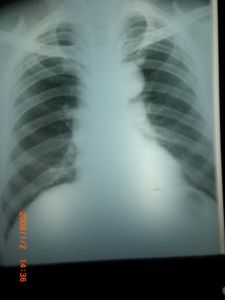

(1)胸部平片:大的食管重複畸形可顯示為後縱隔內緻密度均勻、邊界清楚的軟組織包塊影,使縱隔影增寬或突入胸腔,甚至占據胸腔大部。氣管向對側或前方移位,管腔有時變窄。

①半圓形或三角形囊腫:其長軸與食管一致,三角形陰影系囊腫伸入右肺上中葉間裂,受上中兩葉肺壓迫所致。半圓形為最常見類型,邊緣銳利,大致可占據半個胸腔,壓迫周圍肺組織。縱隔向對側移位。